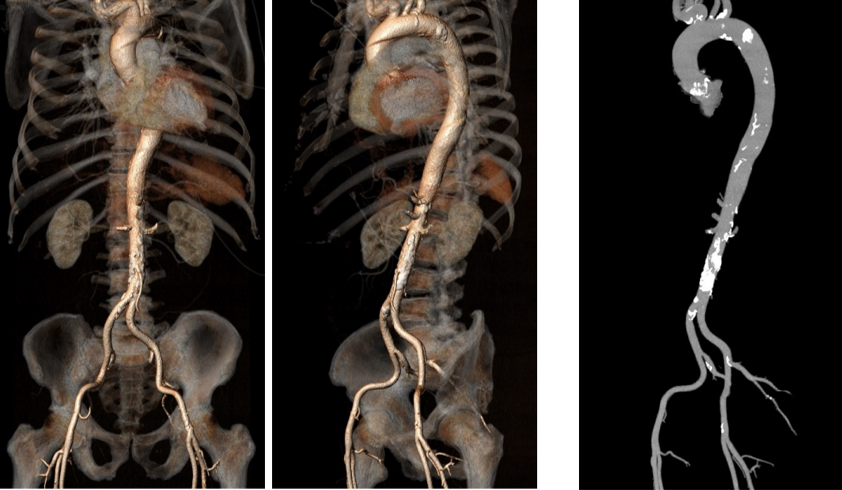

双侧股动脉入路内径可,走行良好,主动脉弓部及腹主动脉可见钙化。